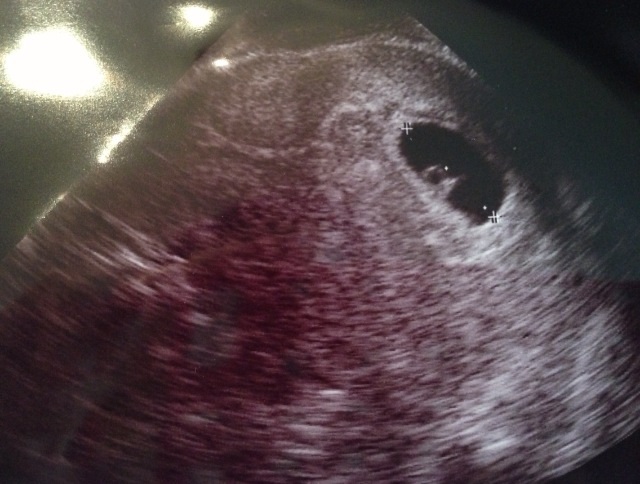

6年ぶりに、妊娠しました!

まだまだタマゴの黄身から、栄養補給中〜

今のトコロ、前回同様ツワリなし。

コドモも順調!

今シーズンは、チャリもスノーボードも出来ないカモ、、、

ぼちぼち、過ごします(≧∇≦)